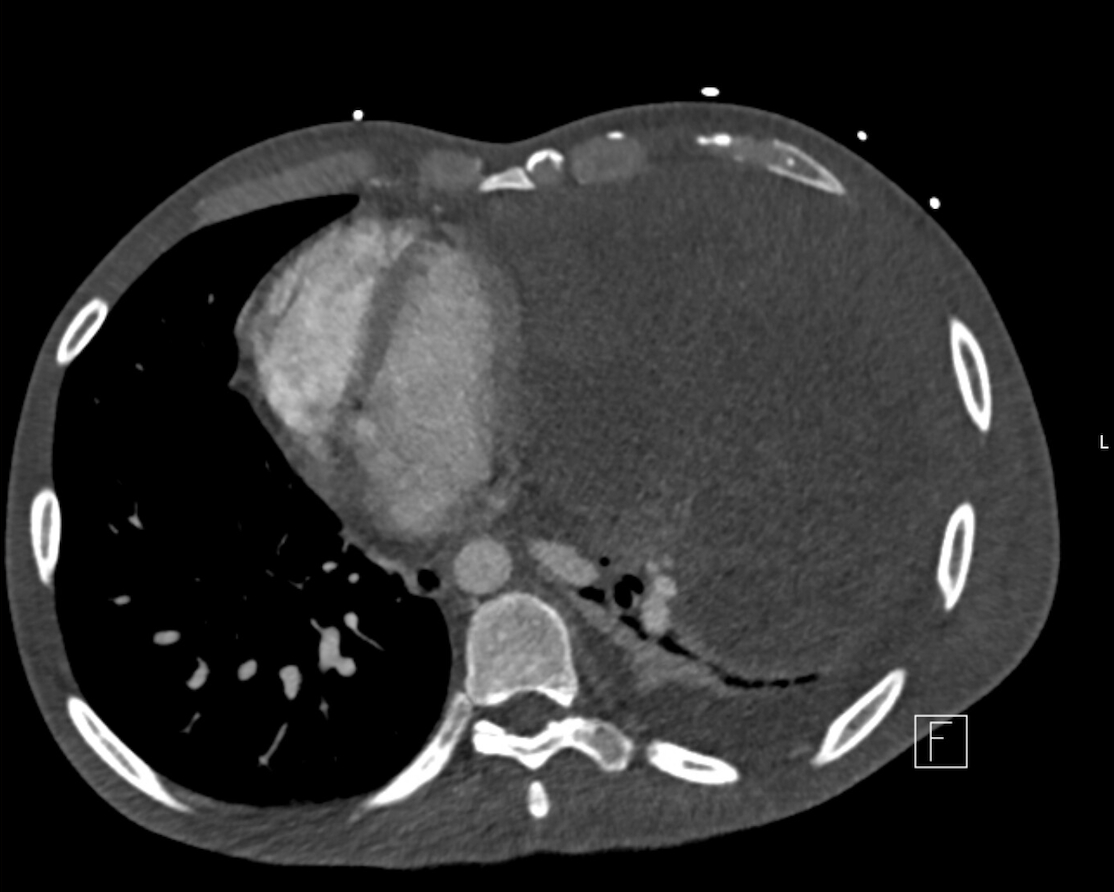

Abstract Body (Do not enter title and authors here): Primary mediastinal embryonal carcinoma is an exceptionally rare and aggressive extragonadal germ cell tumor, comprising less than 2% of mediastinal germ cell neoplasms. Cardiovascular complications, including pericardial effusion and tamponade physiology, are even more infrequent, with only isolated cases reported. We present the case of a 35-year-old male with no significant medical history who presented with progressive dyspnea, pleuritic chest pain, and right shoulder discomfort. Imaging revealed a massive anterior mediastinal mass (21.2 × 14.3 × 20.3 cm) compressing the left lung and shifting mediastinal structures rightward, with direct extension into the left atrium and pulmonary veins (Image 1 and 2). Echocardiography demonstrated a moderate-to-large pericardial effusion with right atrial inversion and respiratory variation in mitral inflow, suggestive of early tamponade (Image 3). However, due to stable hemodynamics and significant distortion of normal anatomy from the tumor mass, pericardiocentesis was deferred as high-risk. Multidisciplinary teams opted for conservative management, and the patient was initiated on systemic chemotherapy with ifosfamide, etoposide, and cisplatin. Serial imaging demonstrated stabilization of the pericardial effusion and early signs of tumor response. Pathology confirmed embryonal carcinoma with elevated tumor markers (AFP 514 ng/mL, β-hCG 158 mIU/mL, LDH 3,078 U/L). Neurological evaluation for multifocal infarcts revealed a brain metastasis and suspected embolic phenomena; vascular imaging showed a left popliteal artery thrombus. The case illustrates a rare instance where both malignant pericardial effusion and external tumor compression contributed to tamponade physiology without overt clinical collapse. It highlights the complexity of managing cardiac involvement in malignancy, where anatomy, mass effect, and clinical stability guide intervention. This case reinforces the need for individualized cardiovascular decision-making and interdisciplinary coordination in rare oncologic presentations involving pericardial pathology.